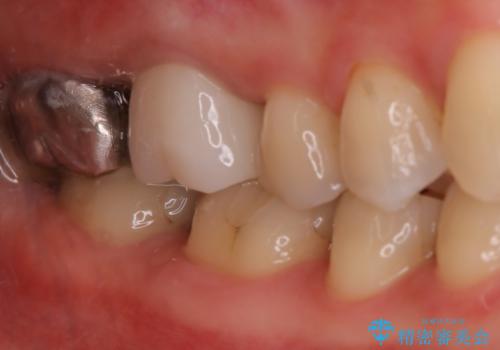

- 元々は別の部位の治療で通われていた患者様でしたが、ニキビのようなものが繰り返しできたり消えたりするとのことで、治療介入を行いました。

根管治療を再度行うことでフィステル(ニキビのようなできもの)は消失しました。最終的にセラミッククラウンによる補綴治療を行いました。